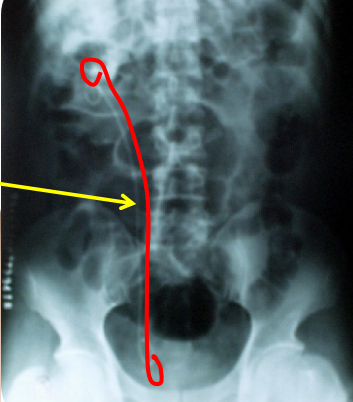

1. 双“J”管是什么

双“J”管是泌尿系统手术后根据需要留置的一种引流管道,因其两端弯曲,形状似字母“J”,故名双“J”管,又因双J管两端卷曲,每端形似猪尾而得名,故又称”猪尾巴管”也叫“输尿管内支架”。

2. 双“J”管放在哪里?

双“J”管有两端,头端位于肾脏(多位于肾盂),尾端位于膀胱,中间的管体位于整个输尿管管腔内。